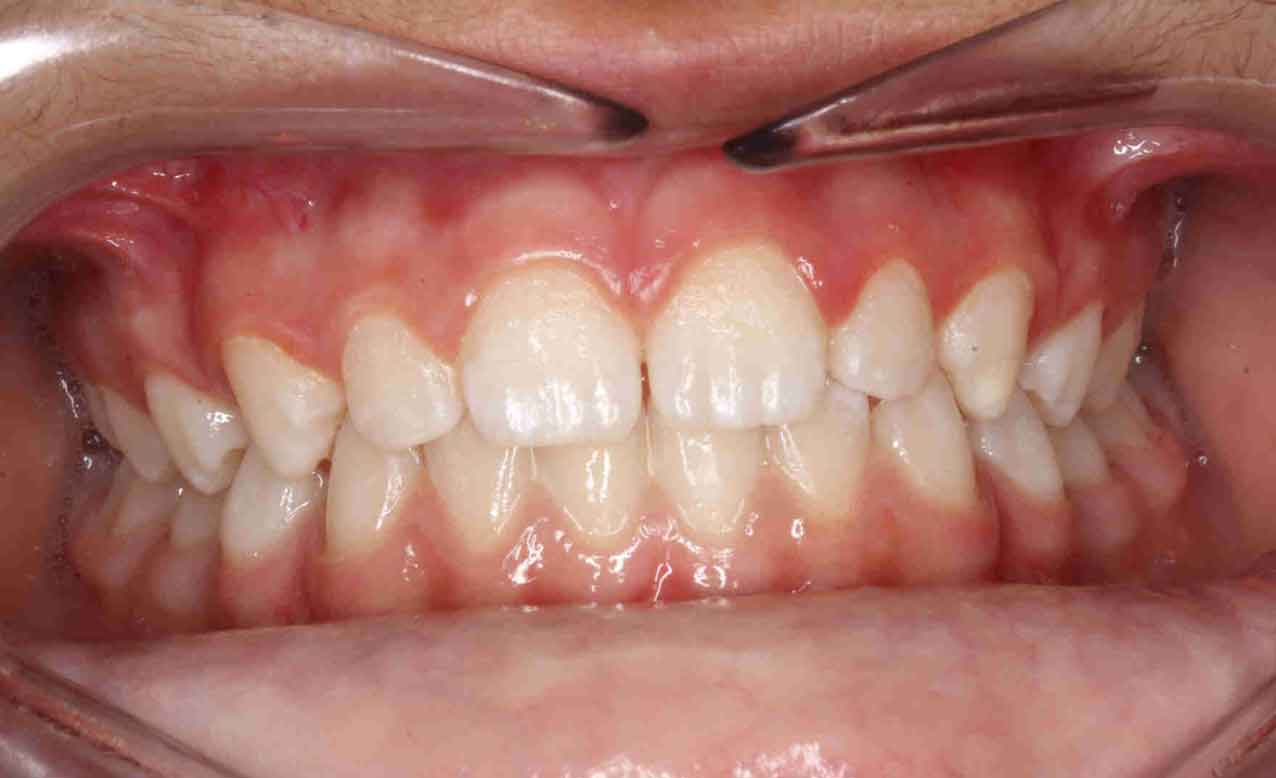

Tratamiento solo interceptivo 1ª Fase

En las siguientes imágenes puedes ver distintos resultados del tratamiento, deslizando la barra central de un lado a otro.